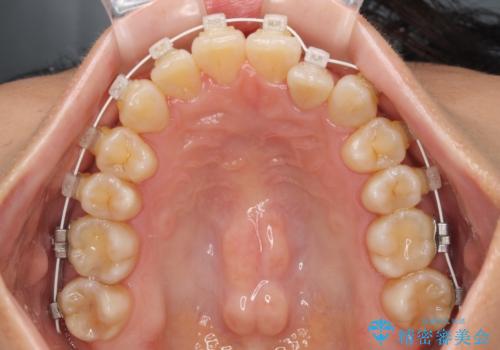

- 矯正装置

- 審美装置

舌のトレーニングをしっかりと行っていただき、補綴治療も含めて1年強の短期間で治療を終えることができました。